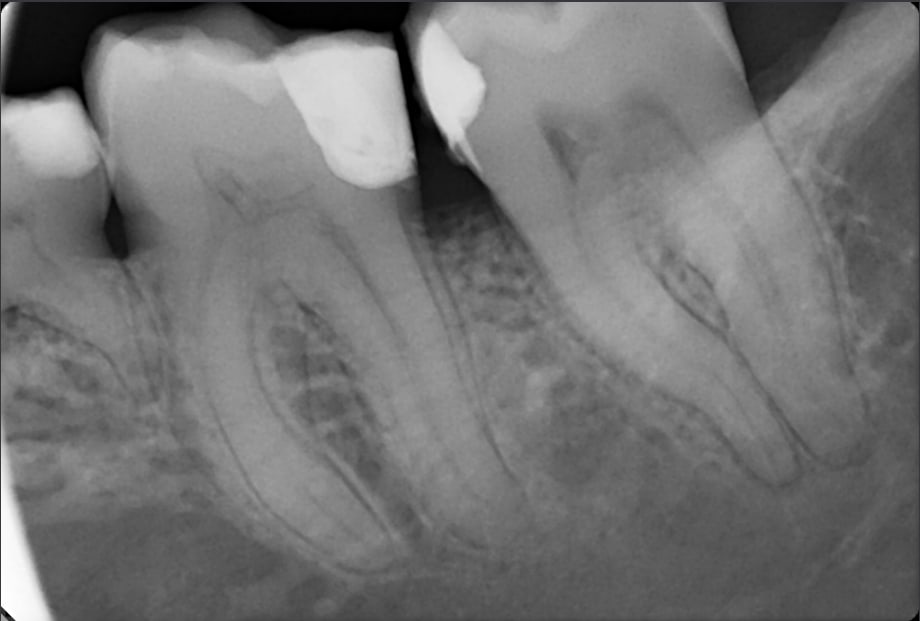

Un bel exemple de la situation en France.

Ce matin ma collab reçoit en consulte une patiente qui se plaint de dlrs intenses de temps en temps suite à la reprise d'un soin par son praticien.

Avec examen, il s'agit d'un simple syndrome du septum. Voyez la Radio.

Difficile de critiquer la qualité des soins qui semblent étanches et surtout sans débordements.

Le point de contact, qui semble absent à la Rx, est très léger en bouche.

Ma collab juge honorablement ne pas pouvoir faire mieux.

Elle la renvoie chez son praticien habituel et conseille le passage de brossettes.

A mon niveau et en y consacrant un peu de temps, je suis certain de pouvoir faire mieux.

On rebombe la face mésiale de la 37 et on reprend le soin OD sur la 36 avec une matrice pré courbée et un anneau.

Problème, on est en France. Pour tout cela, je ne peux même pas facturer la dépose des soins.

Et les nouveaux soins, un 2-faces et un 1-face, nous serrons rémunérés 50€ et 29.30€.

L'inlay serait trop mutilant pour l'instant et son collage délicat vu le niveau de la limite en distal.

Bref il est probable que sans une hygiène adaptée, apparaisse à moyen terme une nouvelle lésion en interprox.

Et que la patiente bénéficie d'un full post - full crown bien de chez nous...